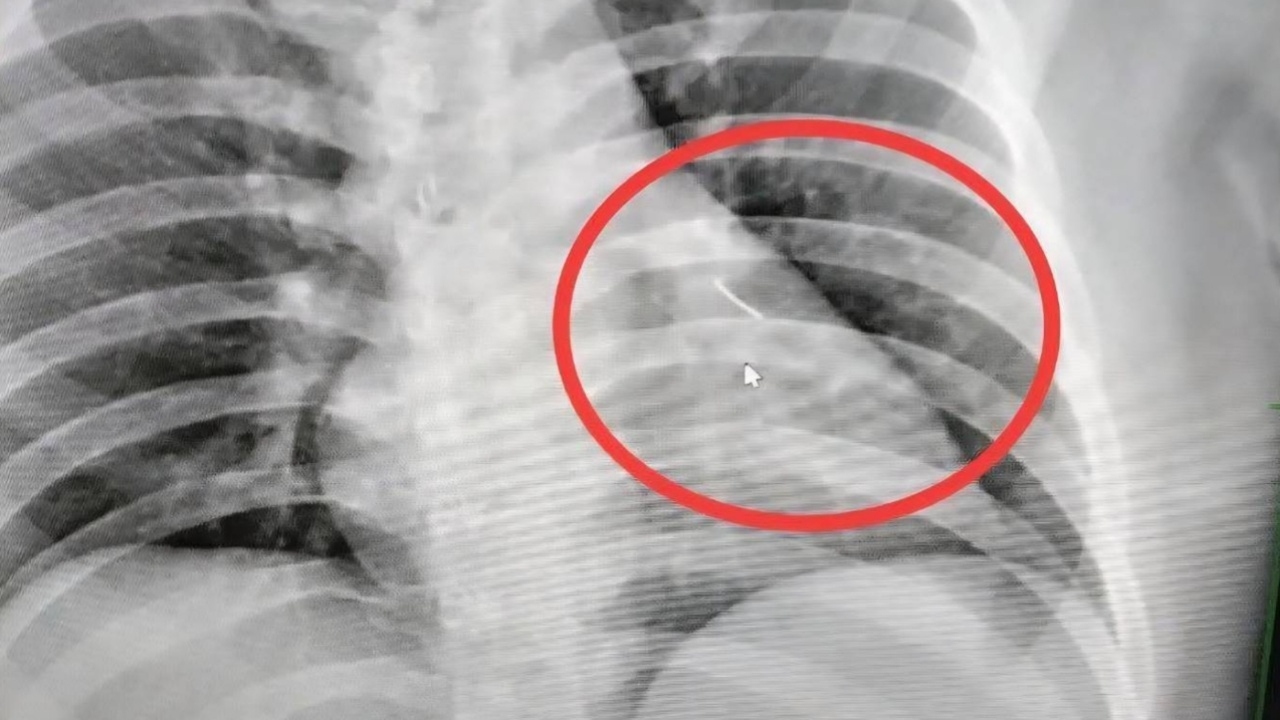

Sau khi chụp X-quang, các bác sĩ phát hiện một cây kim dài 7 cm mắc kẹt trong ngực của người đàn ông, gần như đâm xuyên tim.

Cây kim được phát hiện trong ngực người đàn ông.

Nhân viên bệnh viện đã chụp X-quang và phát hiện một vật thể nhỏ sắc nhọn bên trong cơ thể ông, gần tim. Vật thể này sau đó được xác định là một cây kim dài khoảng 7 cm. Ông Boonlert sau đó được chuyển đến Bệnh viện Buriram để phẫu thuật, các bác sĩ mô tả ca phẫu thuật này phức tạp và có rủi ro cao.